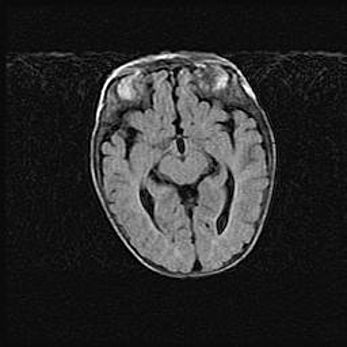

Множественные кисты обоих полушарий головного мозга, наибольшая из них в правой затылочной области. Ассиметричная атрофическая гидроцефалия.

Возраст: 7 месяцев

Вес: 5660 г

Пол: мужской

Окружность головы: 41,5 см

Срок гестации: 28-29 недель

Кисты головного мозга развиваются в результате многоочаговых некрозов вещества мозга и возникают вследствие перенесенной перинатальной инфекции, менингитов, энцефалитов, асфиксии, родовой травмы, расстройств мозгового кровообращения различного генеза. Образованию кист в веществе головного мозга плодов и новорожденных способствуют такие факторы, как высокое содержание в нем воды, недостаточная (или отсутствие) миелинизация и слабая астроглиальная реакция на повреждение.

Кисты могут сочетаться с гидроцефалией и другими поражениями головного мозга.